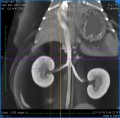

CT ledvin